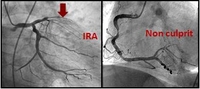

[ACC2015]DANAMI-3:多支冠脉病变完全血运重建安全有效

DANAMI-3试验评估了直接PCI后完全性血运重建是否能够改善多支血管病变患者的预后。对于这一特殊患者人群,可以安全地行完全性血运重建,有助于避免患者以后返院行急诊血管成形术。该方法可以减少对未来血管成形术的需求,但对死亡或再发心脏病发作无明显影响。

2015-03-18